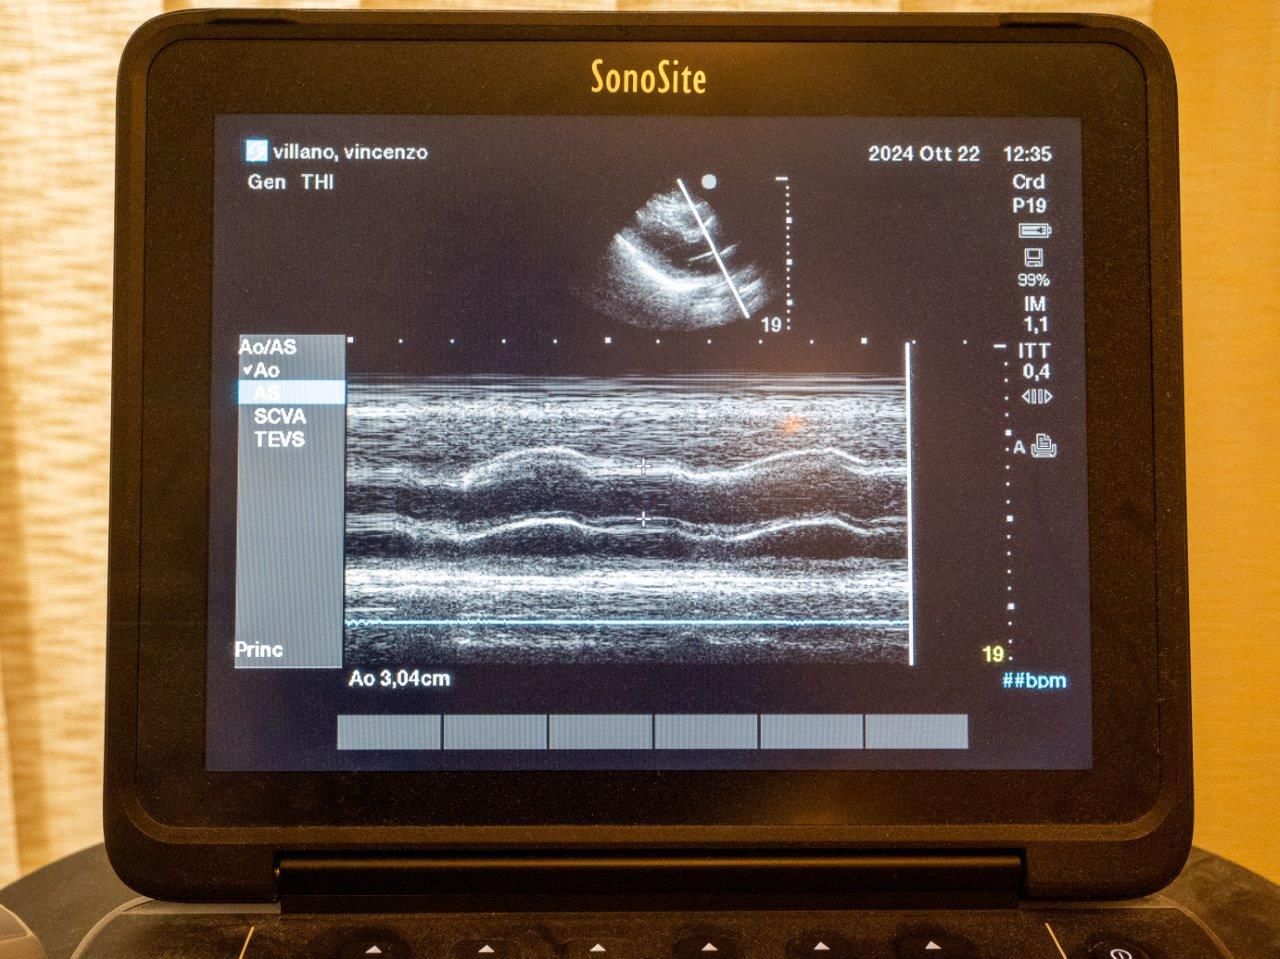

- ecocardiogramma M Mome - 2D - DP - Color-Doppler (anche domiciliare)